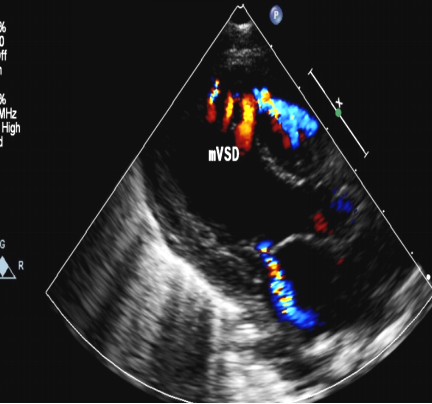

室间隔缺损:超声心动图表现

室间隔缺损(肌部,多发性)

经食管超声心动图监测肌部室间隔缺损镶嵌治疗